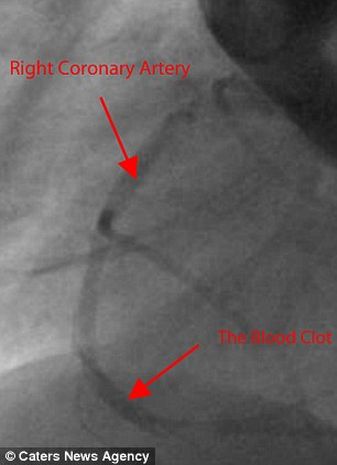

Ο Albert Tensei είναι το μοναδικό παιδί στον κόσμο που υποβλήθηκε σε χειρουργική επέμβαση για την αφαίρεση θρόμβου στην ηλικία των 1,5 ετών.....

Όλα πήγαν καλά.

Η πορεία της υγείας του πηγαίνει πολύ καλ, αυτό δείχνουν οι εξετάσεις που κάνει κατά τακτά χρονικά διαστήματα.